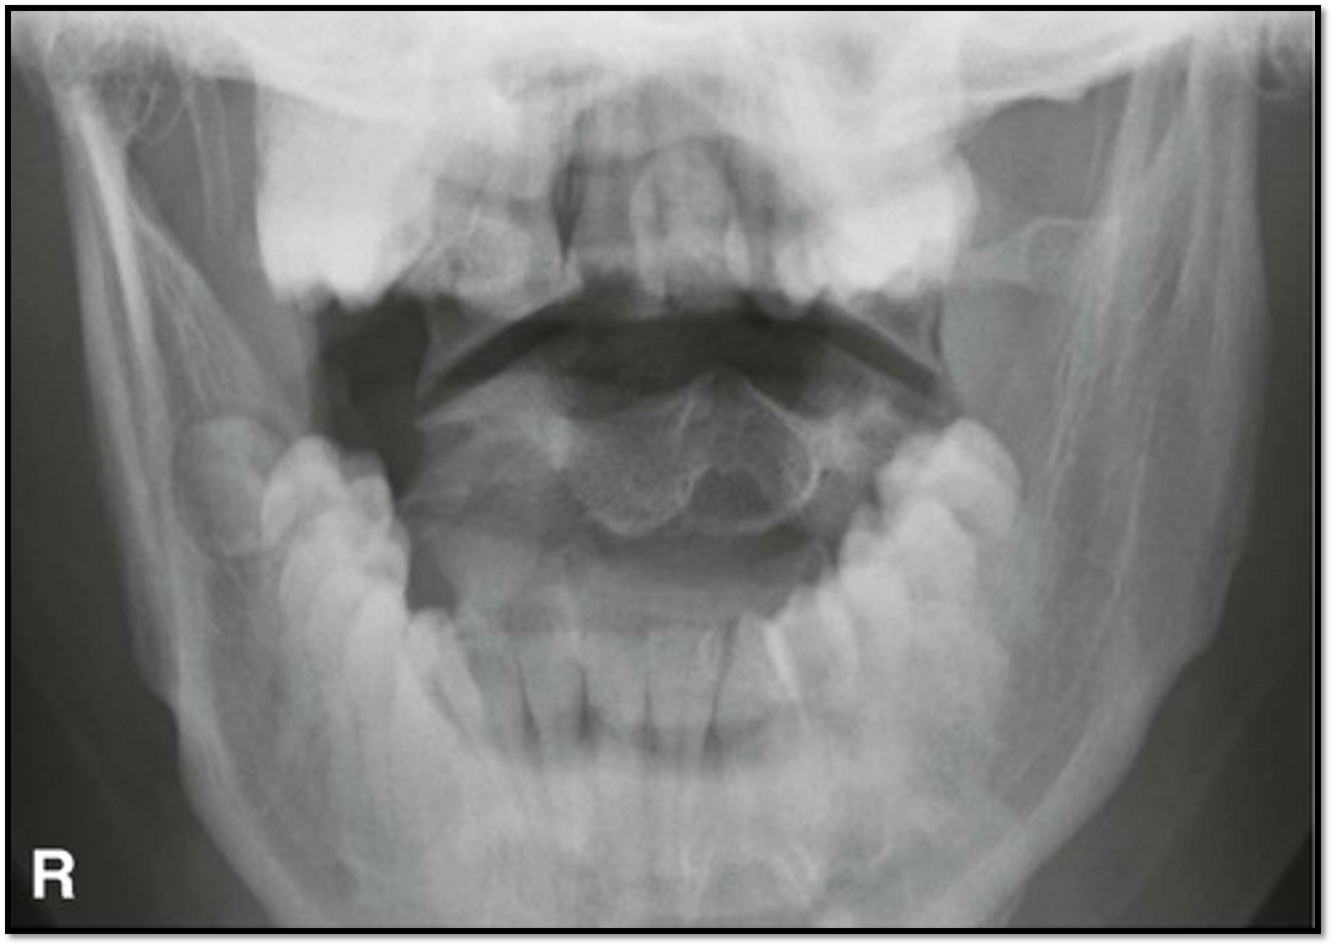

Odontoid Image Criteria

A

• equal distance between dens and lateral masses

• upper incisors aligned with base of skull

• must see lateral edges of C1 and C2

• need to tuck chin

• nose is slightly rotated to the right

Q

• extend the neck and rotate nose to the left

lift chin and rotate nose to the left

tuck chin and rotate nose to the left

tuck chin and rotate nose to the right